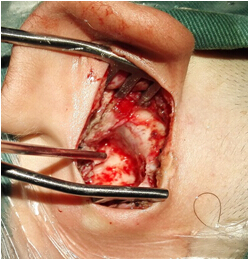

5.膽脂瘤清除后的乳突鼓室腔 6.術(shù)后傷口愈合